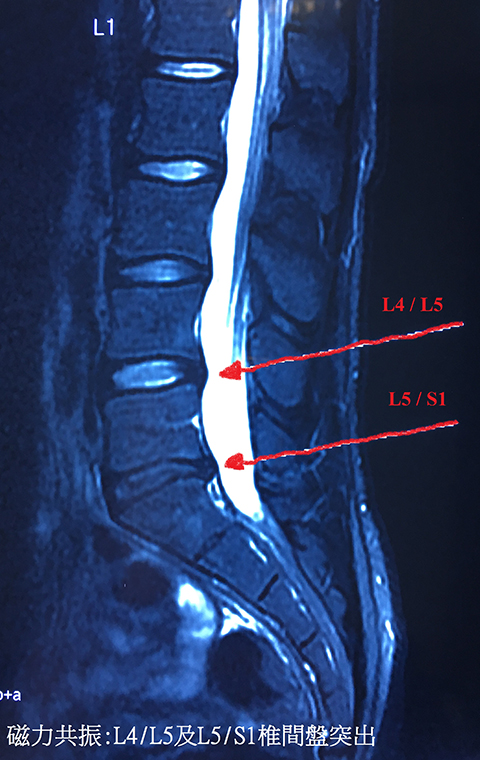

2010年,有一日起身,腰痛到落唔到床,我先生call白車送了我去急症室,打了止痛針後出院。我先生之後迫我去睇骨科醫生,照左磁力共震,報告顯示腰椎L4、L5椎間盤及L5、S1椎間盤突出,突出大概2.5mm。醫生提議做物理治療,最初我有聽話去做的,後來腰好似唔係咁痛,加上我又懶,做左10次8次便沒去了。

2014年3月,我去睇神經科醫生,再照磁力共震,腰椎L4、L5椎間盤及L5、S1椎間盤突出,突出大概3.5mm及4mm,壓住L5神經線,腰患惡化。醫生同我講,你咁多年冇去處理冇去醫,惡化係非常正常。醫生提議手術方案或注射類固醇入脊椎止痛,我選擇後者,諗住可以極速唔痛。打針後,我感覺如重生一樣。